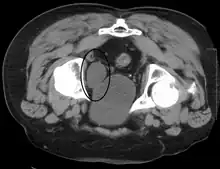

Cross-section of the bladder showing a cancer within it. When a cancer occurs it is most likely to be a transitional cell carcinoma.

Cancer of the bladder is known as bladder cancer. It is usually due to cancer of the urothelium, the cells that line the surface of the bladder. Bladder cancer is more common after the age of 40, and more common in men than women;[29] other risk factors include smoking and exposure to dyes such as aromatic amines and aldehydes.[29] When cancer is present, the most common symptom in an affected person is blood in the urine; a physical medical examination may be otherwise normal, except in late disease.[29] Bladder cancer is most often due to cancer of the cells lining the ureter, called transitional cell carcinoma, although it can more rarely occur as a squamous cell carcinoma if the type of cells lining the urethra have changed due to chronic inflammation, such as due to stones or schistosomiasis.[29]

Investigations performed usually include collecting a sample of urine for an inspection for malignant cells under a microscope, called cytology, as well as medical imaging by a CT urogram or ultrasound.[29] If a concerning lesion is seen, a flexible camera may be inserted into the bladder, called cystoscopy, in order to view the lesion and take a biopsy, and a CT scan will be performed of other body parts (a CT scan of the chest, abdomen and pelvis) to look for additional metastatic lesions.[29]

Treatment depends on the cancer's stage. Cancer present only in the bladder may be removed surgically via cystoscopy; an injection of the chemotherapeutic mitomycin C may be performed at the same time.[29] Cancers that are high grade may be treated with an injection of the BCG vaccine into the bladder wall, and may require surgical removal if it does not resolve.[29] Cancer that is invading through the bladder wall may be managed by complete surgical removal of the bladder (radical cystectomy), with the ureters diverted into a segment of part of ileum connected to a stoma bag on the skin.[29] Prognosis can vary markedly depending on the cancer's stage and grade, with a better prognosis associated with tumours found only in the bladder, that are low grade, that do not invade through the bladder wall, and that is papillary in visual appearance.[29]